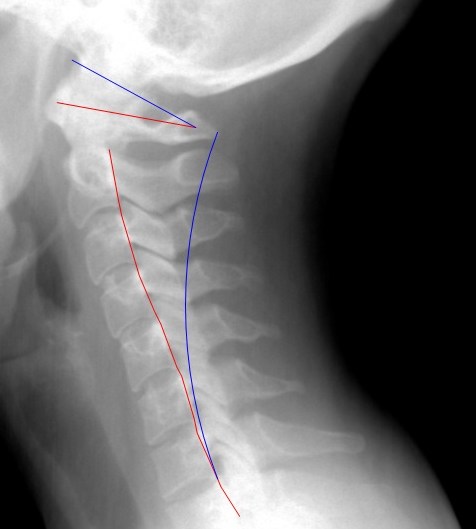

side-view of my neck

The red lines show where my neck is positioned now, the blue ones are where it should be for correct posture and support. I have been in a great deal of pain and sitting at the computer is when it feels the worst.

All of these problems have slowly compounded in my neck over the last year, and a few weeks ago they finally added up to what you see in that picture.